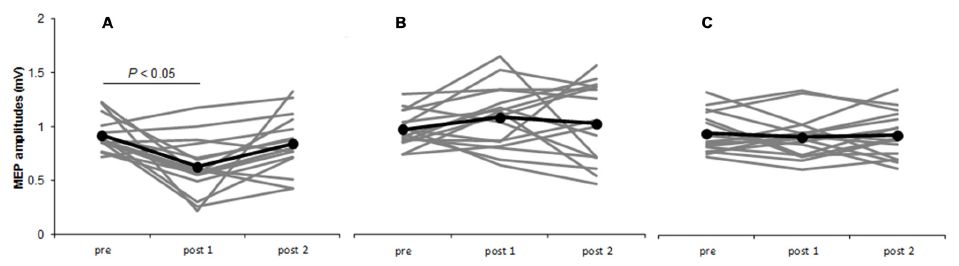

Sasaki R, Miyaguchi S, Kotan S, Kojima S, Kirimoto H, Onishi H. Modulation of cortical inhibitory circuits after cathodal transcranial direct current stimulation over the primary motor cortex. Frontiers in Human Neuroscience. 2016; doi: 10.3389/fnhum.2016.00030.